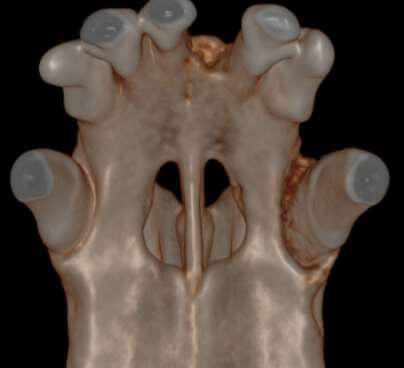

Below: CBCT Hard tissue reconstruction

Below: High intensity CBCT Image

Showing deep bone loss at palatal aspect of upper left canine tooth before an oral nasal fistula has developed